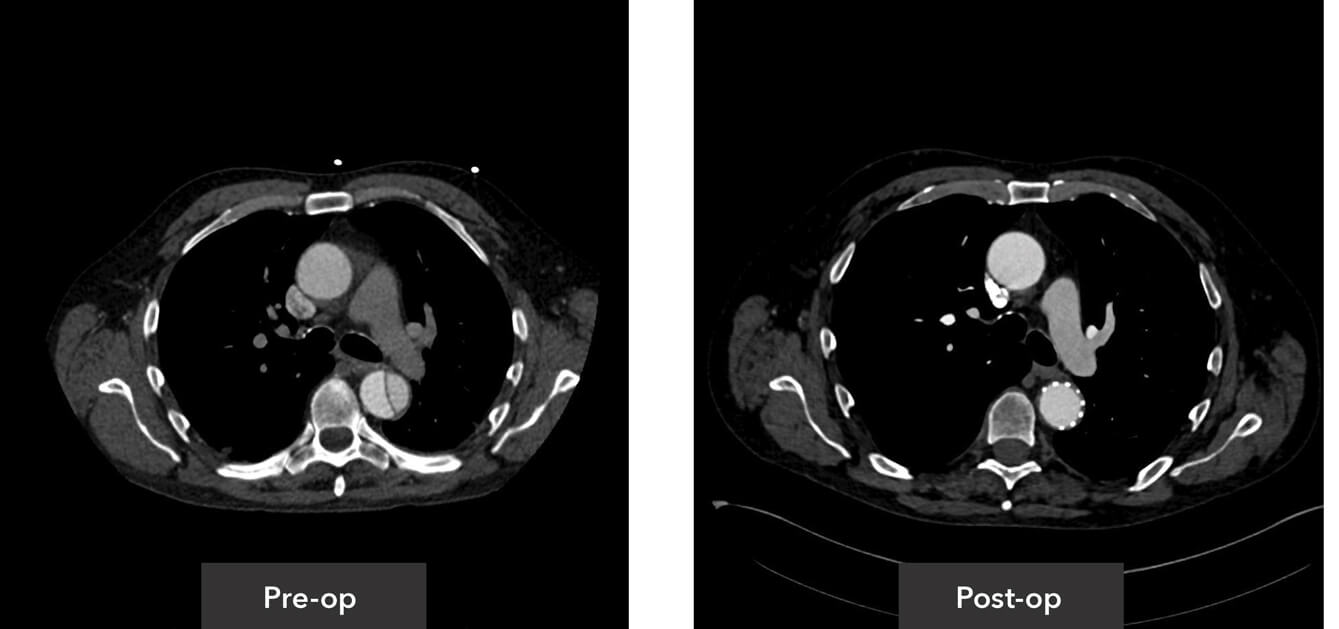

Descending thoracic view pre-op/post-op axial view CT imaging

Visceral segment view pre-op/post-op axial view CT imaging